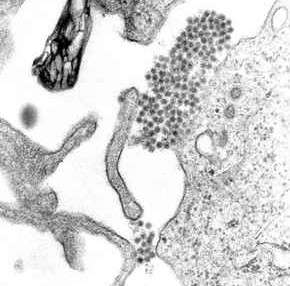

A transmission electron microscopy image showing dengue virus

A TEM micrograph showing dengue virus virions (the cluster of dark dots near the center)

Dengue fever virus (DENV) is an RNA virus of the family Flaviviridae; genus Flavivirus. Other members of the same genus include yellow fever virus, West Nile virus, St. Louis encephalitis virus, Japanese encephalitis virus, tick-borne encephalitis virus, Kyasanur forest disease virus, and Omsk hemorrhagic fever virus.[23] Most are transmitted by arthropods (mosquitoes or ticks), and are therefore also referred to as arboviruses (arthropod-borne viruses).[23]